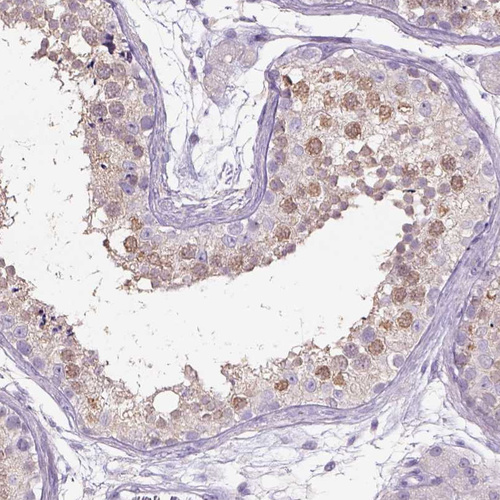

Immunohistochemical staining of human testis shows moderate cytoplasmic positivity in cells in seminiferous ducts.